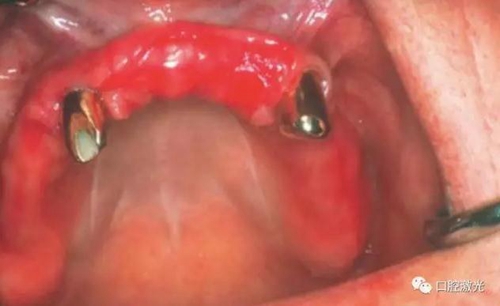

患者女性,43歲。在18年前在13位置上安裝種植體。整個(gè)上顎除23外,牙盡缺失。安裝種植體后,在種植體及23上固定套筒冠義齒。3年后患者發(fā)現(xiàn)刷牙時(shí),臨近13有大量出血現(xiàn)象。通過(guò)探針檢查發(fā)現(xiàn)深度達(dá)6mm。

對(duì)患者實(shí)施局部麻醉,隨后在種植體位置進(jìn)行翻瓣。利用塑料刮治器將肉芽組織清除干凈,并將翻瓣邊緣削薄。此時(shí)在種植體周圍可見明顯骨缺失。